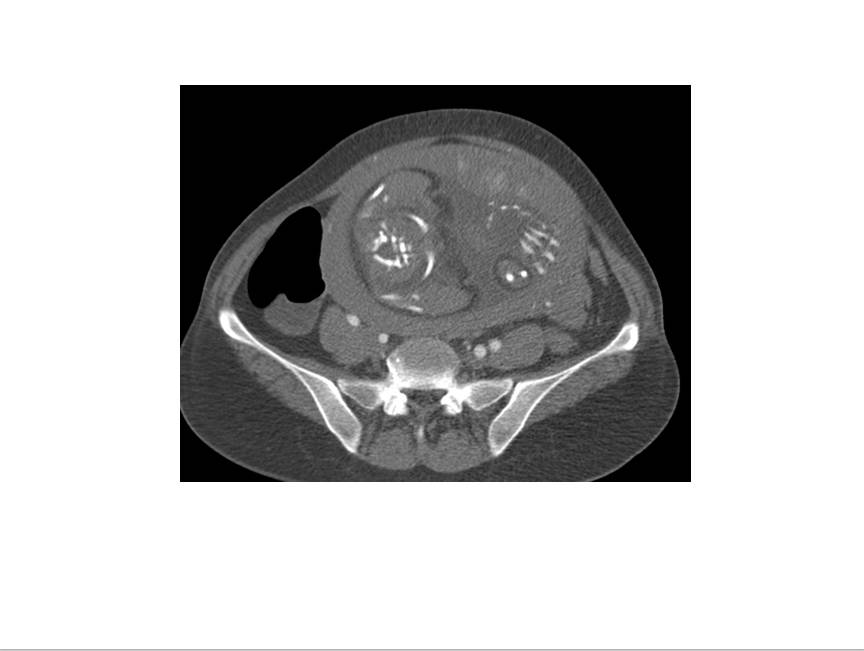

CT表现:自主动脉根部起至腹主动脉肾动脉水平可见撕裂之动脉内膜瓣影,子宫腔内可见胎儿影。

诊断结果:妊娠合并主动脉夹层(I型)。

3、真、假腔的显示:真假腔可同时显影,或假腔强化和排空比真腔延迟;假腔内常有血栓形成可呈略高密度影,当多个破口存在时,真假腔较难区分。一般情况下假腔较大,真腔较小。

4、受累分支及范围:确认分支血管供血状况,观察主要器官的供血血管是发自真腔还是假腔。

显示冠状动脉、头臂动脉、腹腔内脏器动脉及髂动脉起源于真或假腔、是否受压推移。如果受夹层累及,可见内膜片线状充盈缺损影自血管开口处伸入分支血管腔内。